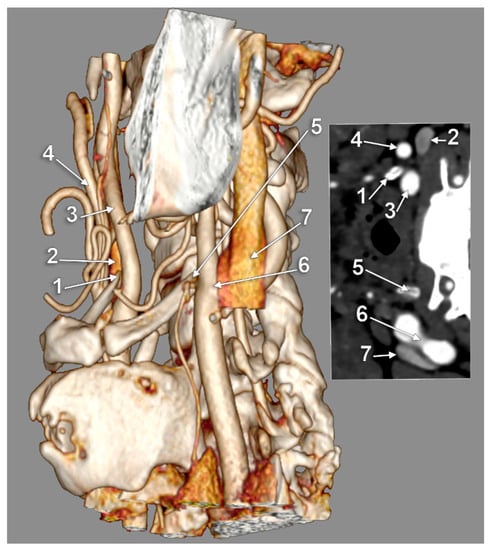

The Carotid–Hyoid Topography Is Variable

3. Results